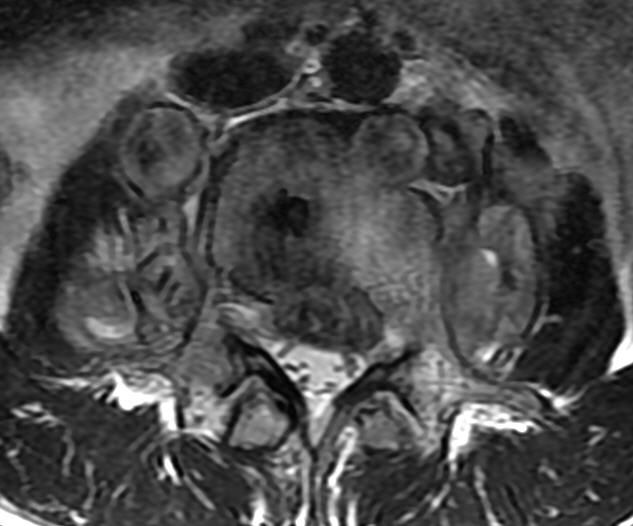

MRI

可提供腰椎管的矢状面、冠状面和轴位横断面上的影像。椎管狭窄以T2加权像显示较好,脑脊液为高信号,产生所谓“脊髓造影”的效果,而骨质增生,骨赘、间盘均为低信号,能清晰地显示椎管狭窄,以及对脊髓的压迫情况。但对肥大的黄韧带、骨质增生等的判断则不如较高清晰度CT扫描。

腰椎正常MRI解剖。

腰椎管狭窄MRI表现。